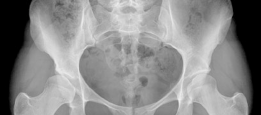

Revision THA Acetabulum: Overcoming Paprosky IIIA & Metallosis

Revision THA Acetabulum Paprosky Type IIIA. ARMD with Metallosis with Severe Periacetabular Osteolysis and Co…